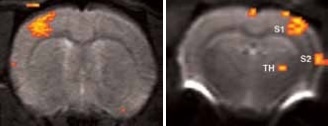

When the forepaw is electrically stimulated, the thalamus, and primary (S1) and secondary (S2) somatosensory corte are activated. To achieve this, electrical pulses (1–2 mA of 0.3 ms duration, at 6 or 3 Hz) are applied for 15 seconds after a resting period of 45 seconds, repeated 5 times. It takes 5 minutes and 45 seconds for the resultant total scan.

Using older DBX electronics and linear surface coils at 7.0 Tesla, BOLD contrast with 400 x 400 x 2000 μm3 resolution can be obtained. Combined with T2-maps, loss of functional activity and its instant recovery as well as stroke lesion (Figure 1) was defined[4,5]. A combination of faster AVANCE II readout electronics, quadrature surface coil, and higher field strength of 11.7 Tesla increased both resolution and SNR to less than 200 x 200 x 2000 μm3, which is more than sufficient to identify the tiny structures along the neuronal activity pathway like the thalamus and secondary somatosensory cortex S2 (Figure 2) with BOLD contrast.

BOLD activation at 11.7 Tesla using the quadrature surface coil with a resolution of (left) 300 x 300 x 2000 μm3 for high quality and (right) 150 x 200 x 2000 μm3 for high sensitivity.

Figure 2. BOLD activation at 11.7 Tesla using the quadrature surface coil with a resolution of (left) 300 x 300 x 2000 μm3 for high quality and (right) 150 x 200 x 2000 μm3 for high sensitivity. Image Credit: Bruker BioSpin Group